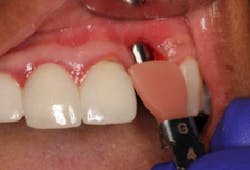

This patient presented with an unrestorable tooth No. 10 due to severe caries (figure 1). Prior to tooth extraction, the patient was informed that in order to avoid having a large defect, additional bone and soft-tissue grafting would be necessary. This type of augmentation would require additional time and finances, as well as increased surgical visits and appointments. The patient was informed that failure to undergo these procedures might result in (1) longer restorations, (2) the need for gingival ceramics, (3) inability to clean the prosthesis, and (4) increased forces on the implant because of the increased crown-to-implant ratio.

Tooth No. 10 was extracted. The socket was disinfected with chloramine-T gauze. An immediate implant (4.3 mm x 10 mm with a 5 mm healing screw) was placed (figure 2).